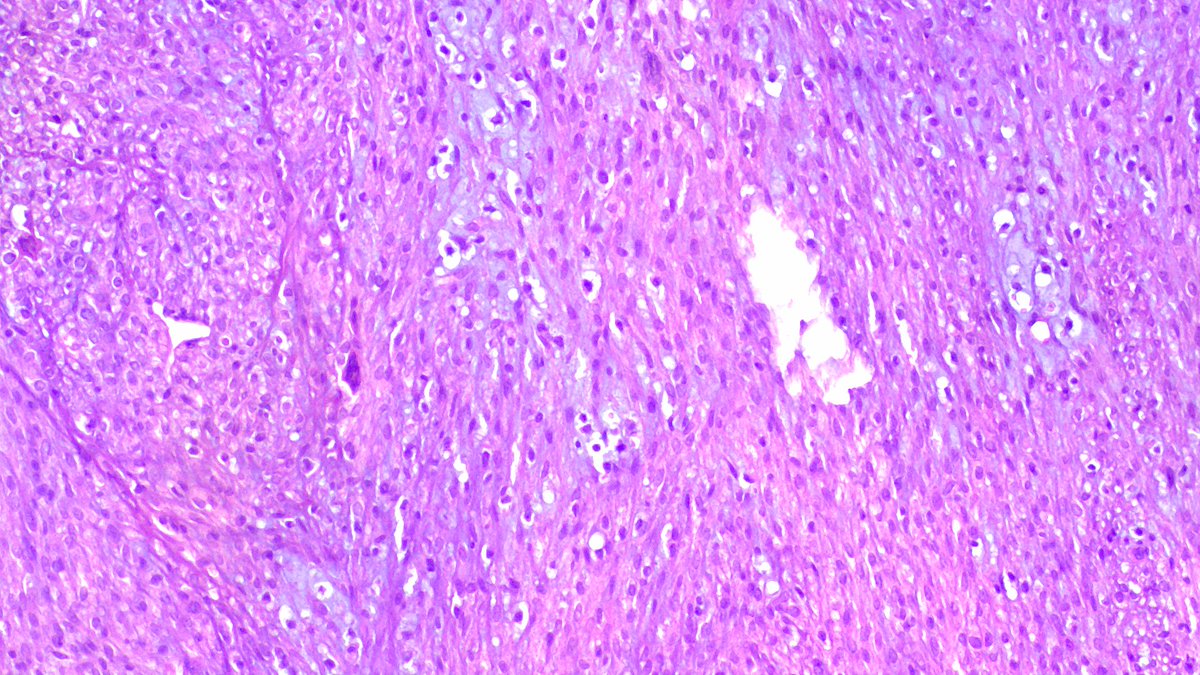

❄️ Frozen to Final: Diagnostic Correlation Case: 75M with massive compressive thyroid mass (9 cm) with tracheal invasion 🧊 Frozen: Malignant tumor (subtype deferred) 💎 Final diagnosis: Medullary Thyroid Carcinoma 🔬 Key features: • Nests, trabeculae, cords • Polygonal cells, granular cytoplasm • Salt & pepper chromatin • Lymphovascular invasion 🧪 IHC: Calcitonin+, CEA+, Synapto+, Chromogranin+, INSM1+ CK7+, CK20-, TTF1 (diffuse) Thyroglobulin–, PAX8– 🧬 Molecular: • Activating RET mutations in majority (germline in hereditary cases – MEN2A/MEN2B; somatic in sporadic) • RAS mutations (HRAS/KRAS) in RET–negative tumors • Routine: recommend RET mutation testing ± germline screening (important for family counseling) 📊 Prognosis: • Variable; worse with: Older age, large tumor, extrathyroidal extension (like tracheal invasion here) and distant metastasis • 10-year survival ~70–80% overall, but ↓ significantly in advanced disease • Calcitonin doubling time = key prognostic marker 💡 Pearl: When morphology & clinical picture mismatch on frozen → call “malignant” & defer typing. IHC + serum calcitonin clinches MTC. #PathTwitter #Surgpath #EndocrinePath #ThyroidPath #MedullaryThyroidCarcinoma #FrozenSection #Histopathology #Pathology Case courtesy @annsmiley78